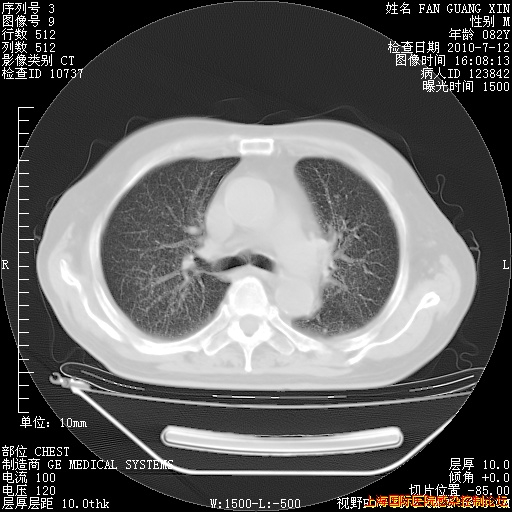

补发6月12日肺部CT肺窗

6月12日肺窗

整整相隔30天的肺部CT好像有所好转啊。甲强龙减量第3天,需要观察体温。

海管,自昨日你和我通完话后,不知您岳父消化道症状有无缓解?体温怎样?阅读7.12日胸部ct,个人认为目前激素治疗是有效的,甲强龙减量是适宜的。因在抗痨治疗,需密切观察肝功、肾功能和血常规。不过,老年、长期住院和大量使用激素,很担心菌群失调发生